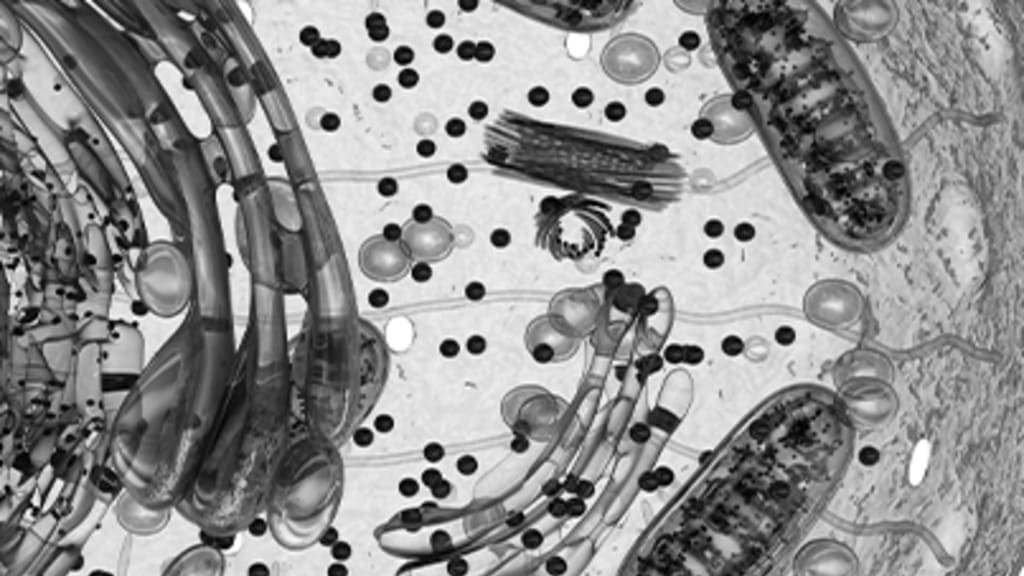

Mikroskopaufnahme

Eine Schlüsseltechnologie, die Leben rettet

2017 gilt als das Jahr des Durchbruchs der Gentherapie. Aggressive Krebsformen, Aids oder auch schwere Erbkrankheiten könnten damit bald geheilt werden. Bei der Gentherapie handelt es sich um eine Schlüsseltechnologie des Gesundheitssektors, der großes Potenzial zugesprochen wird. Auch aus Anlegersicht ein Megatrend, der bald Fahrt aufnehmen wird? Unter der Voraussetzung eines kommerziellen Erfolgs bei entsprechenden Marktakteuren könnte die Technologie dem Portfolio frühzeitig einen innovativen Anstrich verleihen. Nicht nur aufgrund von interessanten Renditechancen, sondern auch aus Gründen der Diversifikation eines klassischen Anlageportfolios, wenn es sich vorwiegend aus Kerninvestments zusammensetzt oder nur «konventionelle Pharmazeutik» enthält.